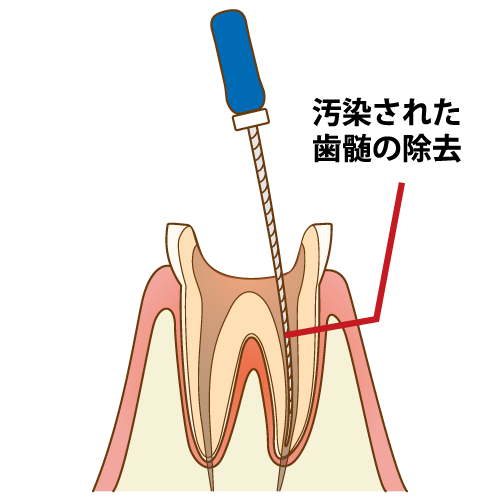

まず先に虫歯を全て取り除きます。虫歯があるとそこから菌が根管内や神経に繁殖するので、菌に汚染された神経など全て除去します。歯の根っこの中にある根管のさらに中の神経を細い針のような器具、あるいは器械で取っていきます。

根管洗浄

神経を取り終わった後は、根管の内部が菌に侵されているので細い器具でお掃除をします。その時に根管の幅も広げていきます。

根管は元々細く洗浄がしにくい状態であり、薬を入れるスペースもありません。洗浄しつつ広げていくことで、細菌を除去しながら消毒液が先端まで行き渡り、薬が緊密に詰められるようにスペースを確保していきます。